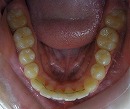

矯正治療前 矯正治療後